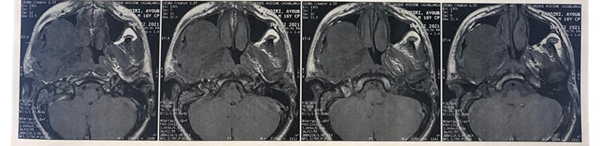

infiltrates the pre-vertebral muscles on the homolateral side. At the top, it

comes into contact with the floor of the orbit, with bone lysis of the anterior

and base of the skull, and infiltrates the homolateral temporal lobe (Figures 7 and 8). Below, it

Figure 7: MRI on coronal section

showing the tumor that comes into contact the floor of the orbit

Figure 8: MRI on coronal section

showing the tumor infiltrating the base of the skull, and the homolateral temporal lobe